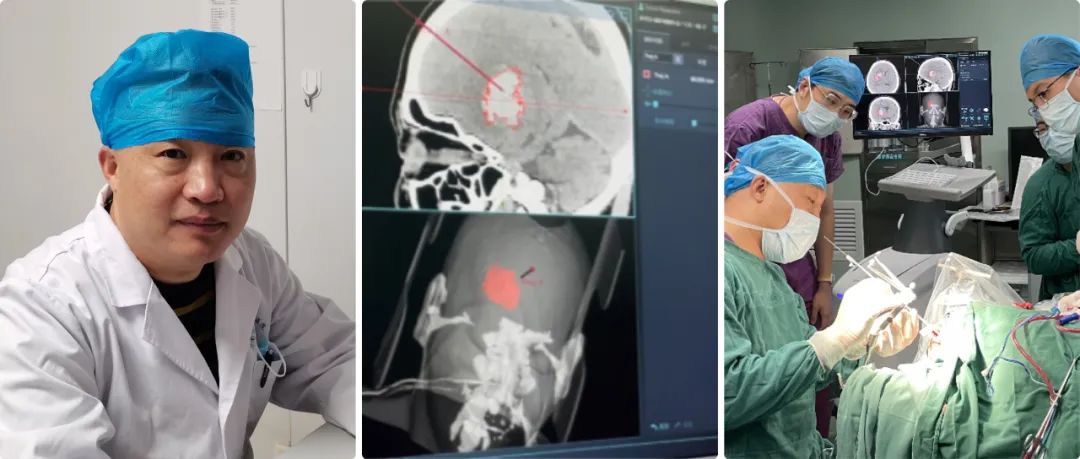

高磊:我院神經(jīng)外科自1998年正式成立,至今經(jīng)過(guò)二十余年的努力,已成為濟(jì)南市濟(jì)陽(yáng)區(qū)人民醫(yī)院發(fā)展最為迅猛的學(xué)科之一??剖议_放床位45張,其中搶救、監(jiān)護(hù)床位5張。年門診量5000余人次,年收治患者2600余人次,每年完成各類手術(shù)400余臺(tái),其中危重的病人手術(shù)170-200例左右。

高磊:隨著現(xiàn)在交通法規(guī)的日益完善,現(xiàn)在顱腦創(chuàng)傷的病人正在逐年的減少,自發(fā)性腦出血的病人卻在逐年的增多,所以科室也從單純的顱腦創(chuàng)傷逐步成為集顯微神經(jīng)外科、立體定向神經(jīng)外科、血管內(nèi)介入神經(jīng)外科等多個(gè)亞學(xué)科的綜合性神經(jīng)外科,下一步以腦血管病為主要救治方向。

但是大部分病人雖然是腦出血,但是病人生命體征比較穩(wěn)定,我們盡可能用神經(jīng)導(dǎo)航來(lái)實(shí)現(xiàn)微創(chuàng)血腫穿刺引流。

神經(jīng)導(dǎo)航微創(chuàng)手術(shù)就避免了傳統(tǒng)開顱手術(shù)的弊端,它可以實(shí)現(xiàn)精準(zhǔn)穿刺血腫引流,病人一次性接受手術(shù),恢復(fù)比較快,并對(duì)病人整體創(chuàng)傷很小。

高磊:準(zhǔn)備做神經(jīng)導(dǎo)航手術(shù)之前,我們給患者進(jìn)行顱腦CT薄層掃描,層厚大約在0.625毫米-1毫米,然后在神經(jīng)導(dǎo)航系統(tǒng)進(jìn)行重建,在重建虛擬像上選擇合適的靶點(diǎn)。

靶點(diǎn)選擇的三個(gè)原則:第一,從頭皮到血腫的穿刺路徑比較短;第二,避開大腦重要功能區(qū);第三避開重要的神經(jīng)血管。

我們經(jīng)過(guò)對(duì)病人注冊(cè),實(shí)現(xiàn)在電腦上與實(shí)際人頭部位置融合,再根據(jù)電腦上確定的穿刺位置,選擇實(shí)際病人顱上的穿刺位置,兩者基本上重合,這樣確保穿刺路徑的精準(zhǔn)性。

高磊:華科精準(zhǔn)這款Sinovation神經(jīng)導(dǎo)航系統(tǒng)功能比較完善/強(qiáng)大的,顱腦CT、核磁共振、血管造影等都能實(shí)現(xiàn)圖像的重建。

高磊:任何手術(shù)設(shè)備,尤其導(dǎo)航系統(tǒng),漂移不可避免;Sinovation神經(jīng)導(dǎo)系統(tǒng)的誤差可以控制在0.5毫米左右。

我們對(duì)腦組織等漂移怎么克服呢?第一精準(zhǔn)定位,第二實(shí)時(shí)導(dǎo)航,就是穿刺點(diǎn)確定后,我們通過(guò)顱骨鉆孔到達(dá)皮層,再進(jìn)行一次注冊(cè)和校正偏差,確保漂移減到最小的程度。

自從引進(jìn)導(dǎo)航系統(tǒng),我們科室技術(shù)水平得到了大幅的提升,正如剛才所講沒有導(dǎo)航之前,我們腦出血都是手術(shù)開顱,徒手穿刺誤差比較大,穿刺效果也比較差,有時(shí)病人的病程住院時(shí)間延長(zhǎng)了,而且效果也不好。

現(xiàn)在我們有了導(dǎo)航,穿刺技術(shù)可以說(shuō)得到了質(zhì)的飛躍;在導(dǎo)航輔助下,基本上可以說(shuō)穿刺百發(fā)百中,病人術(shù)后恢復(fù)也非???,功能改善也非常顯著,科室技術(shù)水平得到了飛躍式的提升,區(qū)域及周邊病人的社會(huì)評(píng)價(jià)也反響很好。